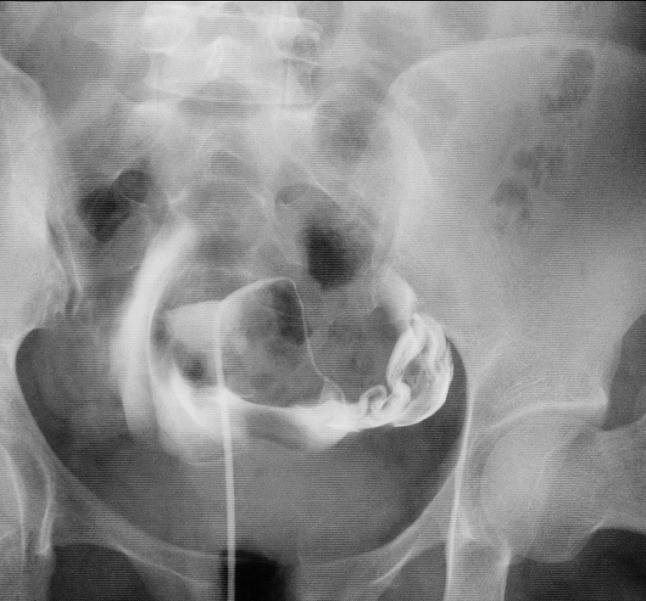

当日她经过激烈的家庭讨论,听说硬是咬牙跺脚从牙缝中挤出来的一万块钱,同意做输卵管介入疏通治疗,我也很感动,决定为他们亲自上手术,最后的治疗的结果是这样的:我觉得她如果能真正遵从医嘱,三个月到半年内应该能够顺利怀孕。